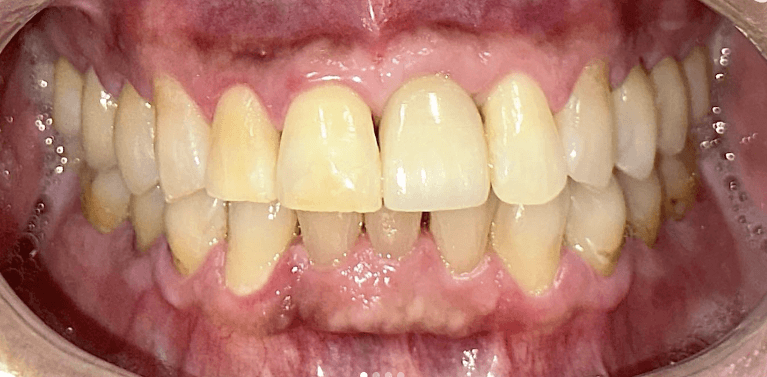

Upper & Lower, All on 4 fixed implant teeth with finals. Patient went home with temp fixed teeth the same day.